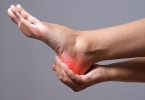

出现骨质退行性变后,建议在医生指导下采用药物治疗,比如依托考昔片、布洛芬缓释胶囊、氟比洛芬凝胶贴膏等,同时也可配合热敷的方法促进局部血液循环,改善症状,对于骨质退行性变症状比较严重者,可采用关节置换术治疗。